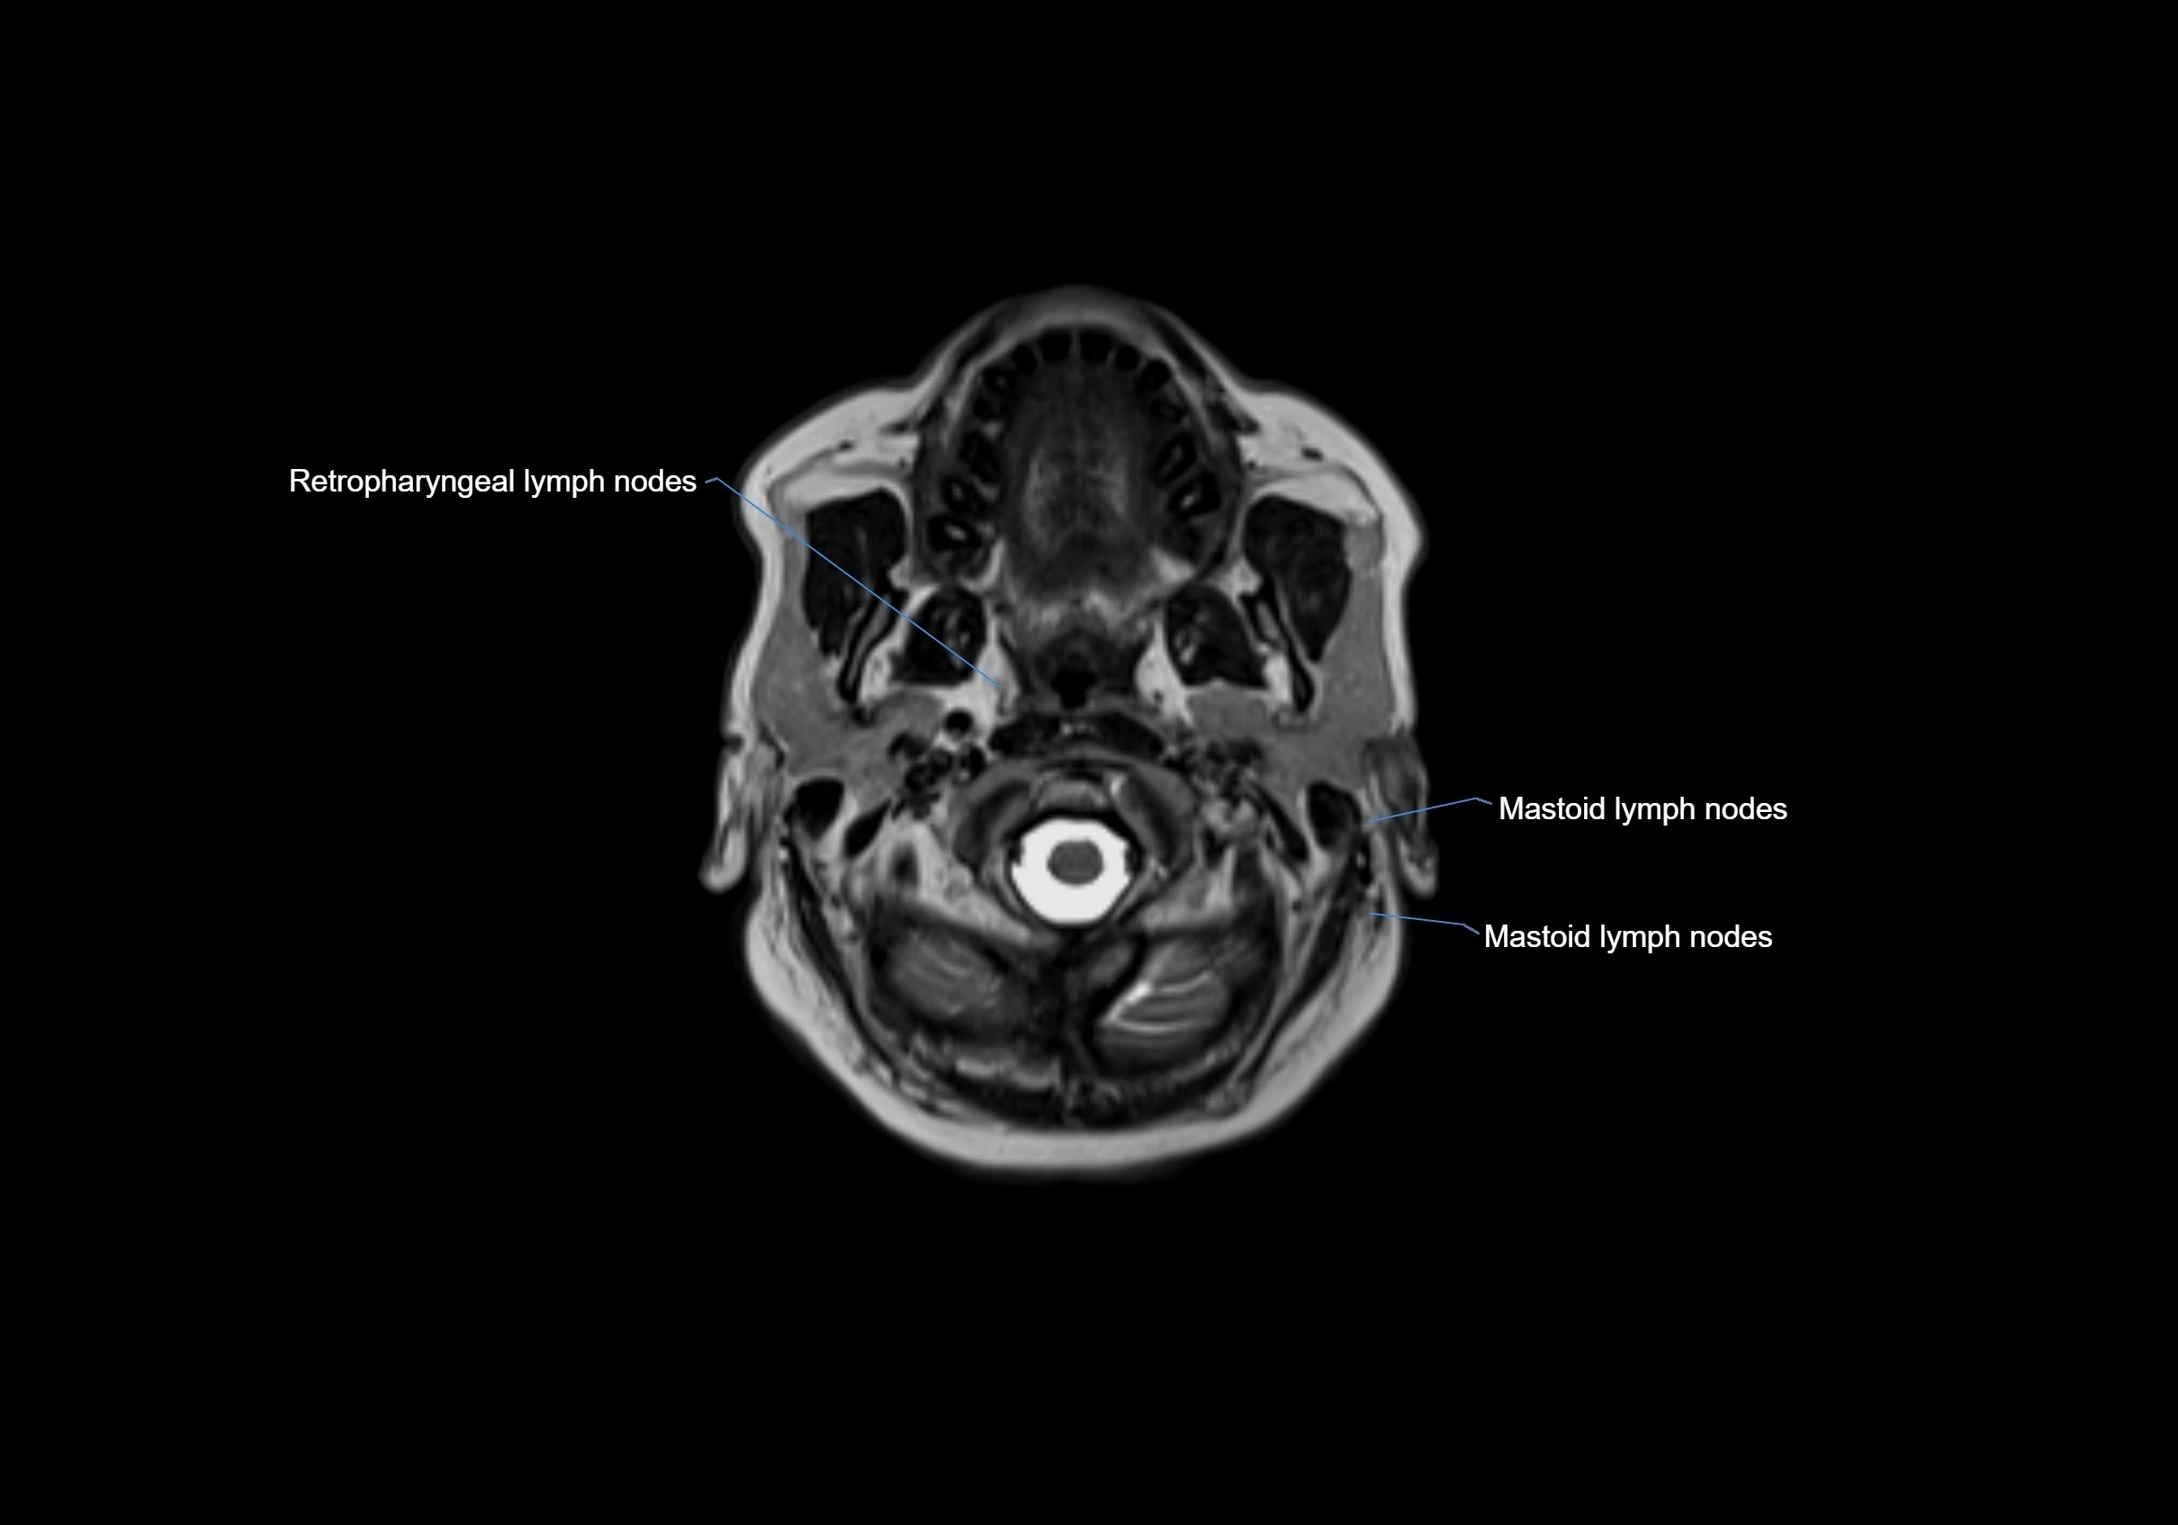

Accessory lymph nodes are small, secondary lymph nodes located along the main facial and cervical lymphatic chains, often adjacent to primary lymph nodes, such as preauricular, submandibular, or occipital nodes. They are typically less than 5 mm in diameter, embedded within subcutaneous fat or connective tissue, and may be variable in number and location. These nodes provide additional filtration and immune surveillance for lymph collected from the face, scalp, and neck regions. Accessory lymph nodes are usually non-palpable in healthy individuals but may enlarge in response to infection, inflammation, or metastasis, making them clinically significant.

Location

• Found along primary lymph node chains, including preauricular, submandibular, parotid, and occipital regions

MRI Appearance

T2-weighted images:

• Nodes show intermediate signal, with surrounding fat bright

• Useful for detecting edema, inflammation, or infiltration

• Fatty hilum may appear slightly hyperintense relative to cortex